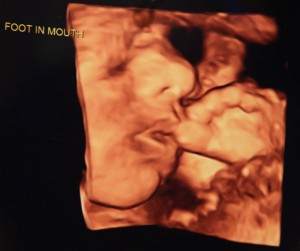

Barberic reports she’s seen kicks that look like dancing, especially with twins.

“I’ve seen legs moving, kicking and head flung back,” she said.

Researchers support these observations, reporting that at 21 weeks there is full kicking – somewhat like martial arts.